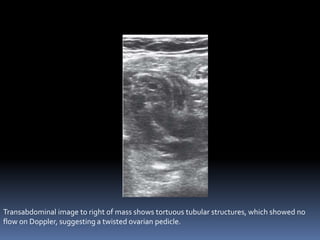

This document contains an image gallery from Dr. Mohit Goel showing various uterine anomalies and ovarian cysts. It includes images of an arcuate and unicornuate uterus, endometritis, a twisted ovarian pedicle, dermoid cysts of varying sizes and echogenicity containing hair, fat, and calcifications, and a combination dermoid cyst showing both mesh and plug structures. The gallery provides ultrasound images of different gynecological conditions for medical education and reference.